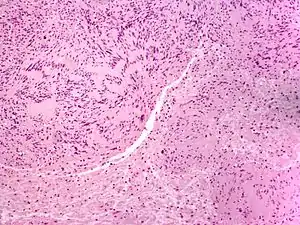

![]() Мікрофотознімок невроми Мікрофотознімок невроми | |